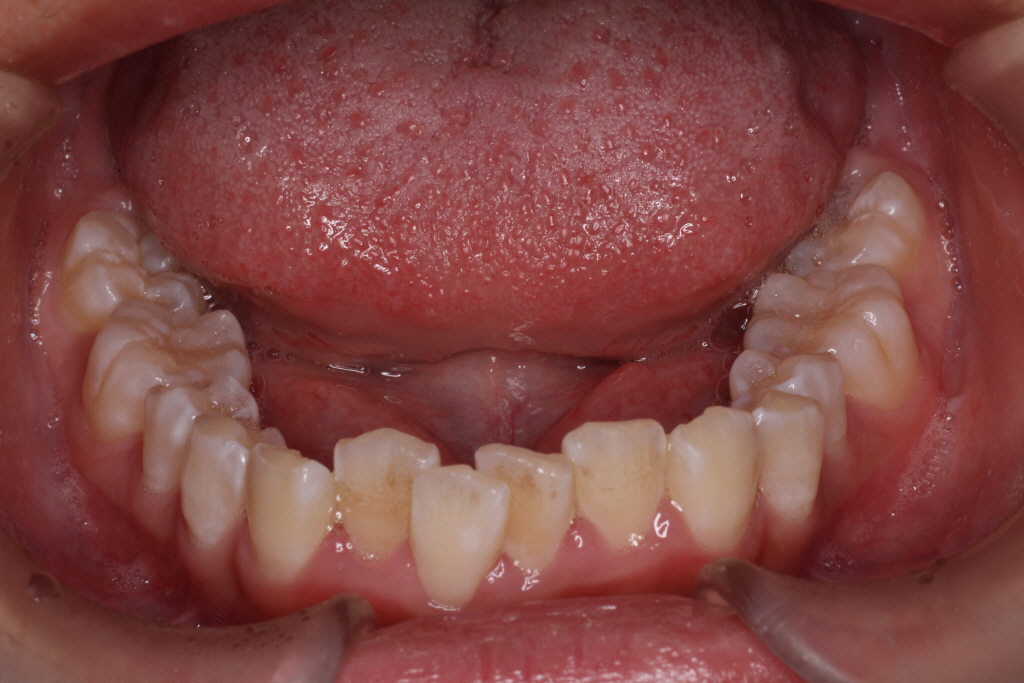

初診時の写真です。

前歯にはがたつき(叢生)がみられ、奥歯は上の歯と下の歯が1歯対1歯で噛んでいることがわかります。

つまり出っ歯の噛み合わせです。

診断:上顎前突・前歯部叢生